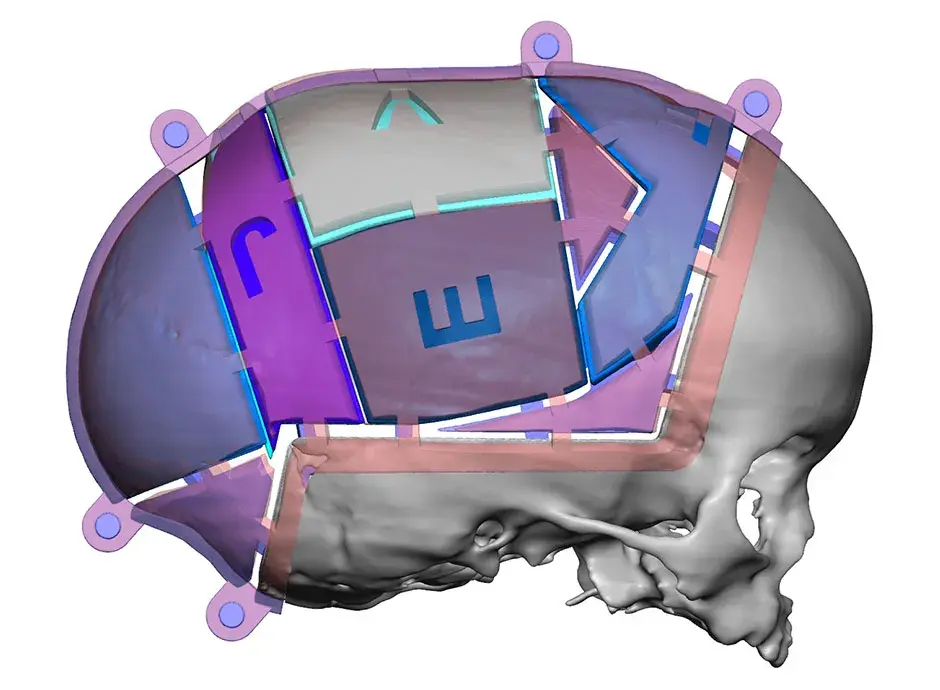

3D Systems' VSP® surgical planning solutions for craniomaxillofacial (CMF) applications received FDA clearance as a service-based approach to personalized surgery over 10 years ago.

3D Systems and Stryker Corporation have partnered to provide surgeons with best-in-class products and services for craniomaxillofacial surgeries. As a leader in personalized healthcare solutions, 3D Systems has planned and delivered devices for more than 140,000 patient-specific cases. The Stryker Craniomaxillofacial business specializes in providing patient-specific options and innovative solutions that help drive efficiencies in surgical suites. The combination of Stryker’s specialized team and advanced implants with 3D Systems' cutting-edge 3D printing technologies and expert consulting services positions both companies to provide a superior level of service to healthcare professionals who use these revolutionary solutions.